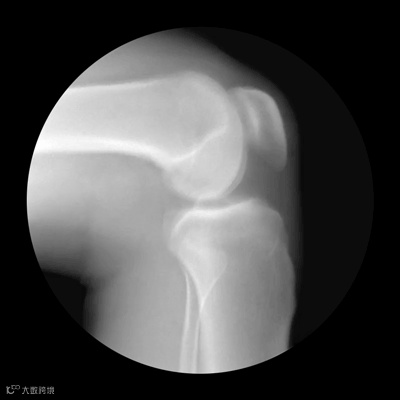

40岁以上的人群应进行骨密度检测,绝经后的妇女更应该重视此项检查。

中老年人在做骨密度检查时,若骨量减少9%以下为骨量正常,骨量减少9%~19%为骨量减少,骨量减少29%~39%则为骨质疏松、骨折危象。